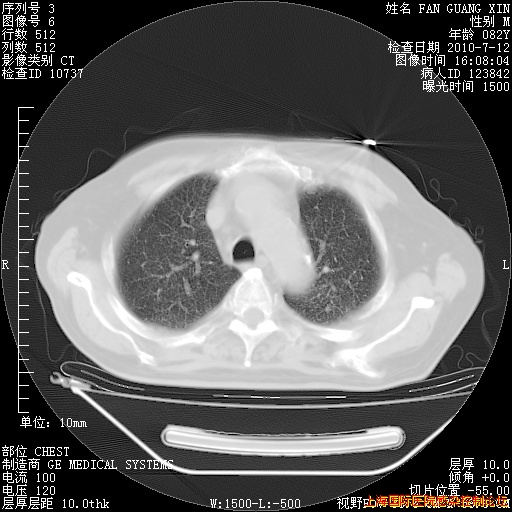

6月12日纵膈窗

整整相隔30天的肺部CT好像有所好转啊。甲强龙减量第3天,需要观察体温。

海管,自昨日你和我通完话后,不知您岳父消化道症状有无缓解?体温怎样?阅读7.12日胸部ct,个人认为目前激素治疗是有效的,甲强龙减量是适宜的。因在抗痨治疗,需密切观察肝功、肾功能和血常规。不过,老年、长期住院和大量使用激素,很担心菌群失调发生